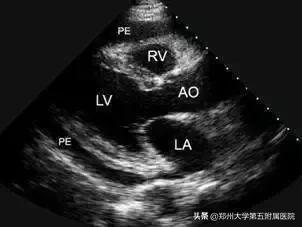

B超是用超声波穿透人体,当声波遇到人体组织时会产生反射波,通过计算反射波成像.超以强度低、频率高、对人体无损伤、无痛苦、显示方法多样而著称,尤其对人体软组织的探测和心血管脏器的血流动力学的观察有其独到之处,如:浅表肿块、血管、穿刺定位等。

5、心脏 常规的心脏结构及功能检查,多选B超,但不能看到心肌内部的变化或异常。冠状动脉粥样硬化和冠心病的筛查可用CT。核磁共振也可用于心脏检查,如:用于确诊断心肌供血或心肌病变类型,更准确的判断左心室肥厚的原因。